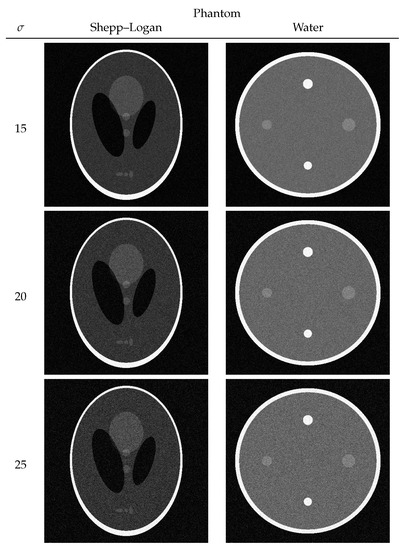

3.1. Numerical Phantom

| Shepp–Logan Phantom | Water Phantom | |||

|---|---|---|---|---|

| 15 | 12.7817 | 90 | 12.3518 | 116 |

| 20 | 13.0832 | 60 | 12.6728 | 66 |

| 25 | 13.3065 | 42 | 12.8896 | 46 |

| SSIM | ||||

| Proposed | Wavelet Transform | |||

| Shepp–Logan Phantom | Water Phantom | Shepp–Logan Phantom | Water Phantom | |

| 15 | 0.7331 | 0.7047 | 0.6781 | 0.6298 |

| 20 | 0.7130 | 0.6826 | 0.6431 | 0.5556 |

| 25 | 0.6968 | 0.6589 | 0.6026 | 0.5198 |